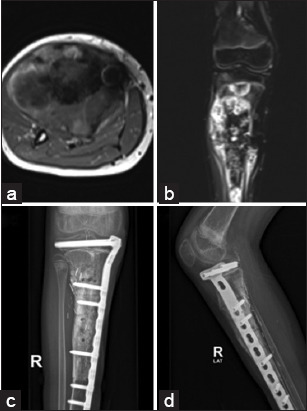

Abstract Image